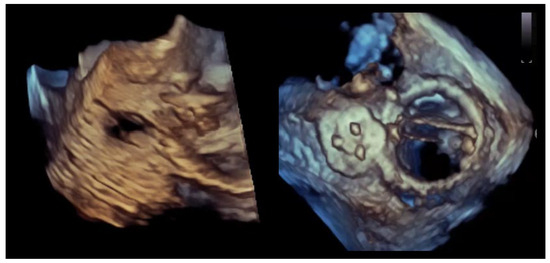

Figure 2.

Crescentic paravalvular leak with elongated annular involvement. (Left panel): Three-dimensional transesophageal echocardiographic reconstruction of the paravalvular region demonstrating an elongated, crescent-shaped defect extending along the prosthetic sewing ring. (Right panel): En-face three-dimensional view illustrating the continuous, non-circular geometry of the paravalvular channel, with multiple potential exit points distributed along the arc of annular dehiscence.